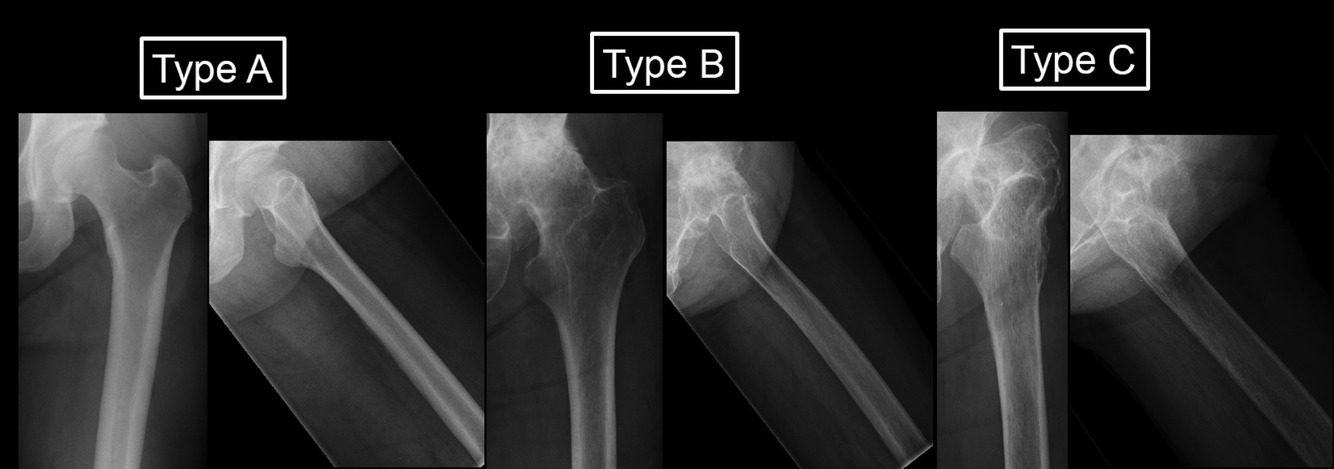

Classification: Dorr

1. What is the Dorr classification?

A

Dorr classification

• is used to evaluate the quality of proximal femoral bone according to radiographic, biochemical and histologic data.

• where it describes the relationship of the diameter of proximal femoral canal relative to diameter of the femoral diaphysis.

• by measuring the ratio between the canal diameter of the femoral diaphysis 10 cm distal to mid point of the Lesser Trochanter and canal diameter at mid point of the Lesser Trochanter.

• and as such divide into 3 types, which is then used as a guide indications for cemented or uncemented femoral component fixation.

• Type A: ratio <0.5, thick bone cortices in AP and lateral views with narrow canal, referred to as “champagne flute”, commonly found in younger patients. Femoral fixation type: Uncemented.

• Type B: ratio 0.5 to 0.75, thining of cortices seen typically at medial and posterior on lateral view, resulting in a widened residual funnel shape canal. Femoral fixation type: Uncemented.

• Type C: >0.75, thinning of cortices on both views, stovepipe shape. Femoral fixation type: Cemented.